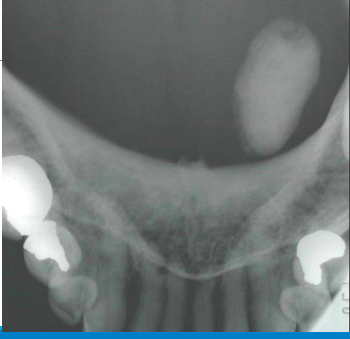

This usually occurs secondary to recurrent or persistent ductal obstruction due to a stone (sialolithiasis) resulting in episodic pain and swelling, usually at mealtime

◦Submandibular involvement may include persistent enlargement